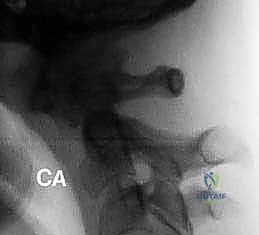

FIG 2 • B. An avulsion ( arrow ) of the transverse ligament from the ring of C1 indicates instability and may require arthrodesis of C1–2.